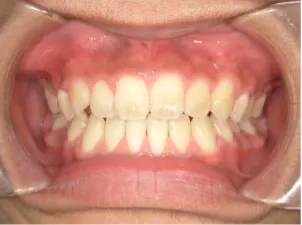

治療中③中1:拡大・前歯の並替え、トイシャー(出っ歯を治す装置)終了

*出っ歯、過蓋咬合、口唇閉鎖不全の改善

*咬合治療用モノブロック装置(筋機能的咬合誘導装置)へ移行

*口唇閉鎖不全がなおり奇麗な口元に改善

*就寝時に使用するモノブロック装置(筋機能的咬合誘導装置)